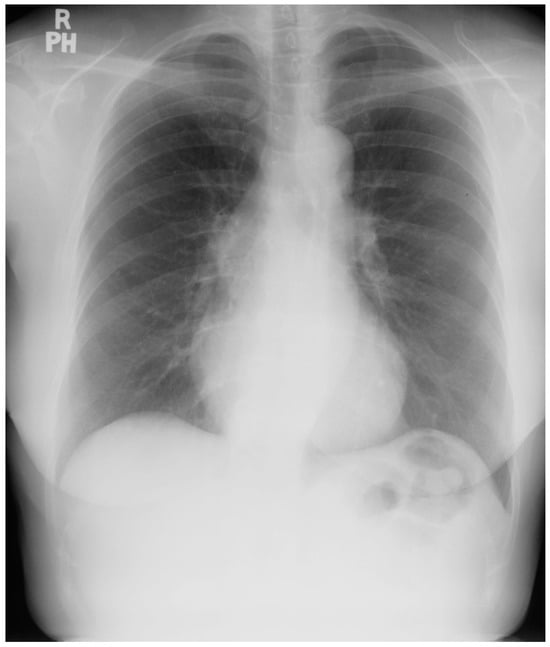

Figure 9.

Posteroanterior chest X-ray of sinus venosus atrial septal defect. This chest X-ray is of a 24-year-old female with a sinus venosus atrial septal defect and anomalous right upper pulmonary venous drainage to the superior vena cava. The image is well centered and there is a good inspiration. The cardiothoracic ratio is increased, the pulmonary artery segment is increased and the pulmonary vascularity is plethoric. Also note that there is a right-sided aortic arch (blue dots). This allows the enlarged pulmonary trunk to be better visualized because the thoracic aorta does not obscure it. Because she had dyspnea, fatigue and exercise intolerance she underwent surgical repair of the ASD and redirection of the right upper pulmonary vein to the left atrium. Her postoperative CXR showed decrease in C-T ratio and pulmonary vascularity. Her symptoms resolved.